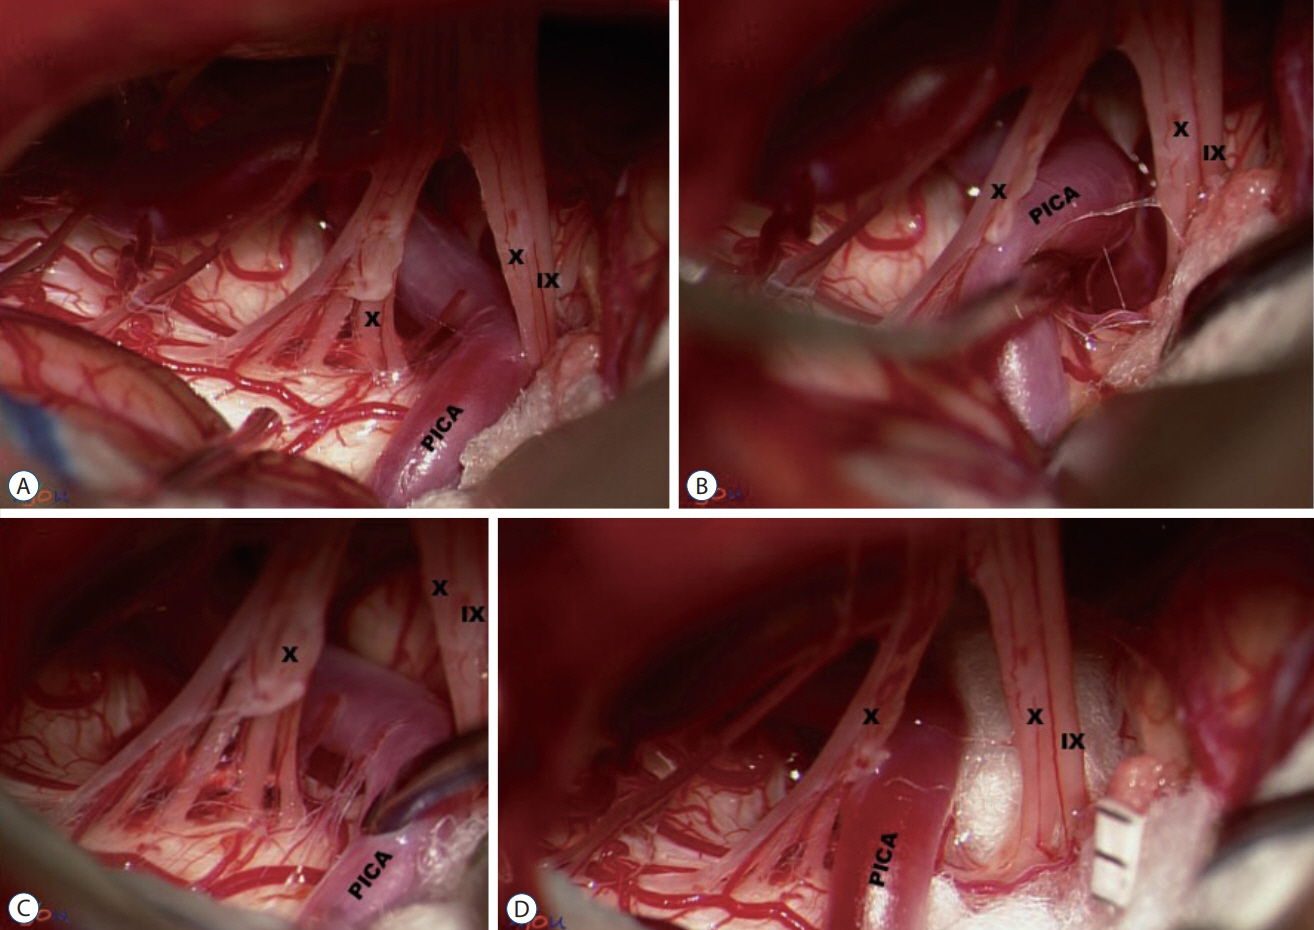

- Glossopharyngeal neuralgia (GPN) is a rare disease that must be differentiated from trigeminal neuralgia. The purpose of this article is to provide a comprehensive review of anatomy, pathophysiology, diagnostic criteria, and several options of treatment for GPN. Lessons learned through our experience of treating GPN are presented in detail, as well as cases of misdiagnosis and diagnostic pitfalls. Microvascular decompression (MVD) should be primarily considered for medically intractable GPN. Techniques employed in MVD for GPN are categorized and described. Especially, we underscore the advantages of the ‘transposition’ technique where insulating material is positioned ‘off’ the root entry zone (REZ), instead of ‘on’ it. We believe this ‘off-the-REZ’ technique can fundamentally prevent recurrence, if applicable. In addition, Gamma Knife radiosurgery can be an alternative option when a patient is ineligible for MVD, though it is categorized as a destructive procedure.